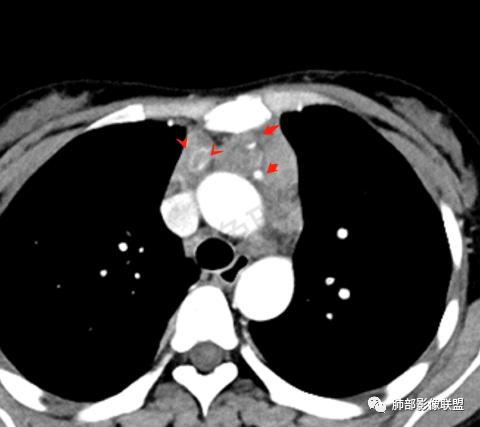

青年女性,贫血病史,前纵隔占位,增强病灶中度强化,可见血管包埋,考虑恶性病变,淋巴瘤,生殖类肿瘤待排除。

定位前纵隔,肿块整体偏软,包绕血管,中度强化,中央坏死,腋窝淋巴结肿大,考虑恶性,考虑弥漫大B,鉴别胸腺癌(年龄不太支持)。

青年女性,前纵隔不规则软组织肿块,呈结节样融合,密度不均匀,见多发坏死,肿块包绕肺动脉主干,呈不均匀强化,多发低密度坏死无强化,内可见血管穿行,伴腋窝淋巴结肿大,考虑淋巴瘤可能大

年轻女性,乏力贫血,前中纵隔肿块,有多结节融合趋势,中度强化,坏死区边界清楚,左内乳淋巴结及双腋窝淋巴结肿大,考虑淋巴瘤。

年轻女性 前中纵隔多发肿块,质软,相互融合,向下侵及心包。增强不均匀强化,内见血管影。双侧腋下多组淋巴结肿大。考虑恶性,淋巴瘤,胸腺瘤。

前纵隔占位,多结节融合,内见坏死,坏死边缘清晰,内乳淋巴结及腋窝淋巴结肿大,包绕血管,贫血,年轻女性,考虑淋巴瘤,鉴别生殖细胞瘤,肉瘤

青年女性,前纵隔肿块,呈多结节融合状,内多发囊变坏死区,血管包埋,双侧腋窝淋巴结肿大,考虑胸腺淋巴瘤可能性大

前纵隔软组织肿块,融合,见多发坏死,强化不均,包绕血管,腋窝淋巴结肿大,考虑淋巴瘤

女,27岁,贫血,前纵隔不规则形软组织密度肿块影,边界欠清晰,其内密度不均匀,部分血管包埋,双侧腋窝见肿大淋巴结,考虑淋巴瘤可能。

前纵隔胸腺结节及肿块,融合,包绕大血管,不均匀强化,多发坏死,边界清,血管包埋,双侧腋窝肿大淋巴结,考虑淋巴瘤

前纵隔不规则肿块,似多结节融合,包绕血管,不规则强化,考虑淋巴瘤

年轻女性,前纵隔多发淋巴结肿大融合,包绕心脏大血管,血管穿行。伴中纵隔、双侧腋窝淋巴结增大,考虑恶性,淋巴瘤可能大。

前纵隔占位,多结节融合,血管穿行,侵犯心包,考虑淋巴瘤

晨读前纵隔多发结节融合成团,包绕大血管,增强内有血管穿行,考虑淋巴瘤,鉴别胸腺肿瘤。

前上纵隔不规则肿块,多结节融合,边界欠清,多发坏死,腋窝多发大小不等淋巴结肿大,年轻女性,考虑恶性,淋巴瘤首先考虑,胸腺肿瘤不除外

前纵隔占位,多结节融合,多发坏死,边界欠清,血管包埋其中,不均匀强化腋窝见增大淋巴结影,首先考虑淋巴瘤,生殖类肿瘤待排!

前纵隔不规则肿块,结节融合,边界不清,平扫密度欠均匀,增强多发低密度坏死,血管穿行,腋窝多发大小不等淋巴结肿大,年轻女性,贫血,发热。考虑恶性:胸腺癌。其次淋巴瘤

纵隔肿块,密度不均,边界模糊,侵及心包。增强不均匀强化,内见血管影。双侧腋下多组淋巴结肿大。考虑淋巴瘤,胸腺瘤,鉴别结核。

纵隔多发结节堆积 塑型生长  质软 边界不清 强化不均  双侧腋窝淋巴结肿大

年轻女性,贫血伴乏力,前纵隔占位,多发结节融合成块,爬孵感,边界模糊,不均匀强化,中心坏死,内可见血管造影,部分侵犯心包,双侧腋窝多发肿大淋巴结,首先考虑淋巴瘤

年轻女性,贫血,CT示前纵隔团片状软组织占位,多结节堆积感,塑形生长,边界欠清,包绕大血管及心包,增强明显不均匀强化,内见血管漂浮。纵隔4R,5,7区及双侧腋窝多发肿大淋巴结,综合考虑为淋巴瘤可能

前纵隔不规则肿块,多结节融合,边界欠清,延周围脂肪间隙生长,包绕主动脉及肺动脉血管,平扫密度欠均匀,增强扫描可见多发低密度坏死,并可见一条血管穿行,腋窝多发大小不等淋巴结肿大,年轻女性,考虑恶性:淋巴瘤,胸腺癌,肉瘤,浆细胞瘤

前纵隔占位,血管包埋,轻中度强化,考虑淋巴瘤。

年轻,前纵隔多结节融合样大肿块,包绕心脏大血管,伴中纵隔、双侧腋窝淋巴结增大,考虑淋巴瘤

女,27,间断头晕、乏力3年,左眼视物模糊2月。贫血。胸部CT:前纵隔不规则肿块,多结节融合,边界不清,沿主动脉及肺动脉间隙生长,平扫密度欠均匀,增强扫描可见多发低密度坏死,纵隔血管供血穿行,腋窝多发大小不等淋巴结肿大。考虑恶性病变,胸腺癌?肉瘤?淋巴瘤?鉴别胸腺瘤、结节病等。

前纵隔和双侧腋窝多发的淋巴结肿大,前纵隔为甚,融合呈中等强化,部分坏死呈低密度,包埋肺动脉主干和左心缘,融合斑块状,内见血管飘浮特点,前纵隔脂肪间隙混浊,首选淋巴瘤!

临床:年轻女性,慢性病程,多系统病变,头晕,贫血,视物模糊。

CT:定位纵膈病变,前中纵隔多发肿块,质软,塑形,密度不均匀,边界清楚。增强不均匀强化,坏死边界清楚,血管漂浮征。双侧腋下多组淋巴结肿大,明显异常强化。

2.影像显示前纵隔不规则块状影,依势贴附心脏大血管旁,密度不均,边界不甚清楚,有结节融合感。

3.病灶轻度不均匀强化,可见血管穿行,散在液性低密度区。

双肺门未见肿大淋巴结。

4.双侧腋窝区见增大淋巴结,边界清楚。

1.年轻女性,前纵隔不规则块状影,密度不均,边界不甚清楚,有结节融合感,轻度不均匀强化,可见血管穿行,最常见最符合的无疑是淋巴瘤!